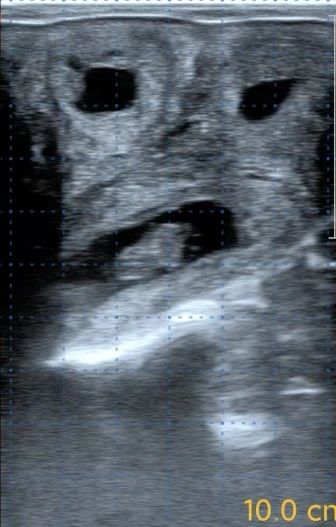

图6 定时输精时优势卵泡

图7 发情期卵巢状态

(左侧:子宫状态;右侧:成熟卵泡)